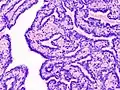

Гістопатологія інтрадуктальної папіломи молочної залози шляхом ексцизійної біопсії,забарвлення H&E